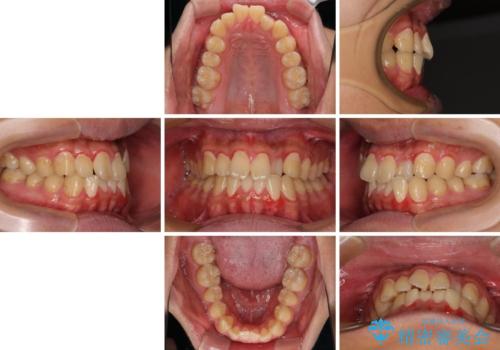

- 前歯のデコボコとクロスバイトを気にして来院された患者様です。

クロスバイトはありましたが、叢生の程度としては酷くなかったため、ワイヤー矯正でもマウスピース矯正でも、好きな方を選択していただきました。

気になっていたクロスバイトは速やかに改善され、1年間で治療を終えることができました。

治療開始前は汚れが多く、全体的に歯肉が腫れていましたが、矯正治療を通して腫れも少しずつ改善されました。